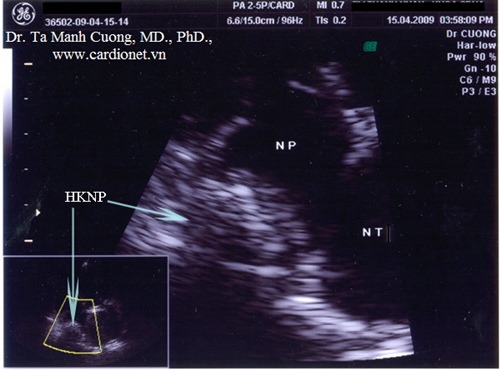

Hình ảnh huyết khối nhĩ phải ở một bệnh nhân van tim nhân tạo đang dùng thuốc chống đông AVK với INR = 2,5...

(pkmc.info) - Nam 27 tuổi, mang van hai lá và van động mạch chủ cơ học, rung nhĩ. Đang được dùng thuốc chống đông loại kháng vitamin K (AVK) với INR = 2.5. Làm siêu âm tim kiểm tra thường quy thấy các van tim nhân tạo hoạt động bình thường. Khi kiểm tra buồng nhĩ phải thì thấy có hình ảnh huyết khối...

Khi phóng to hình ảnh, huyết khối được nhìn thấy rõ hơn trong nhĩ phải.